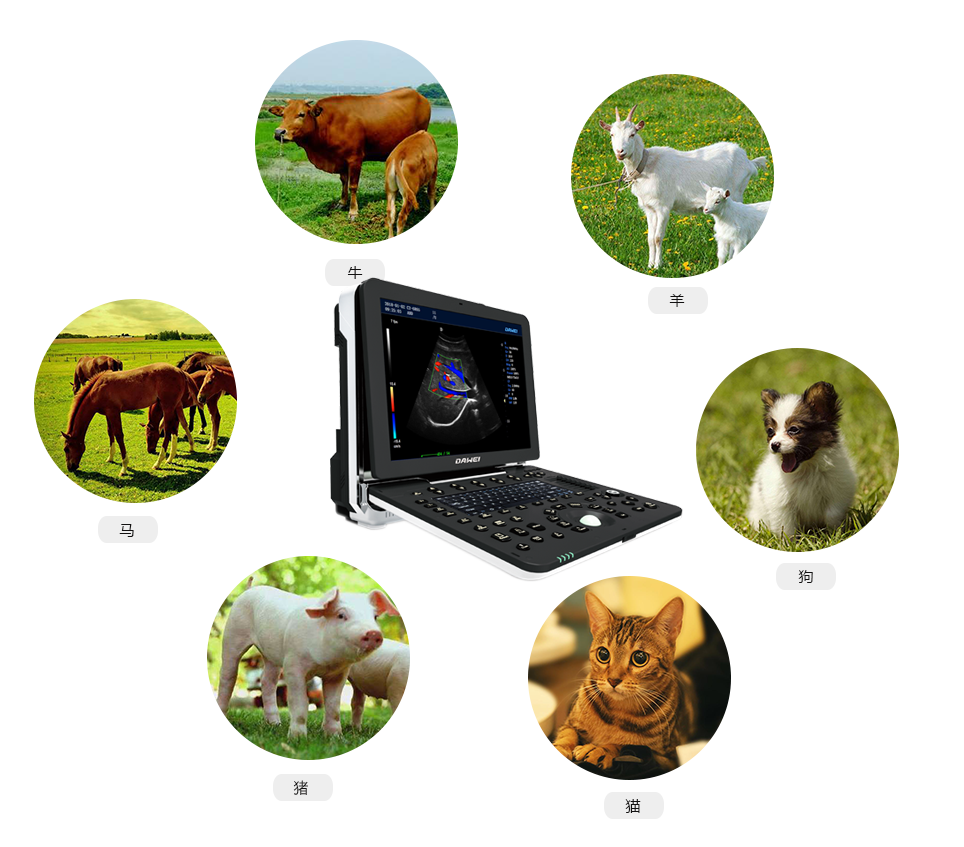

P5-VET便攜手提式獸用彩超機(jī)

全數(shù)字彩色動(dòng)物超聲診斷儀

彩色多普勒動(dòng)物寵物超聲診斷儀

P5-VET獸用彩超機(jī)出色的獸用臨床應(yīng)用

P5-VET高清便攜式獸用彩超機(jī)是一款高清晰度,功能全面的彩色多普勒獸用超聲診斷儀,它可以滿足滿足寵物醫(yī)院及科研機(jī)構(gòu)在消化系統(tǒng)、生殖系統(tǒng)、泌尿系統(tǒng)、體檢及其它方面的檢查和診斷。